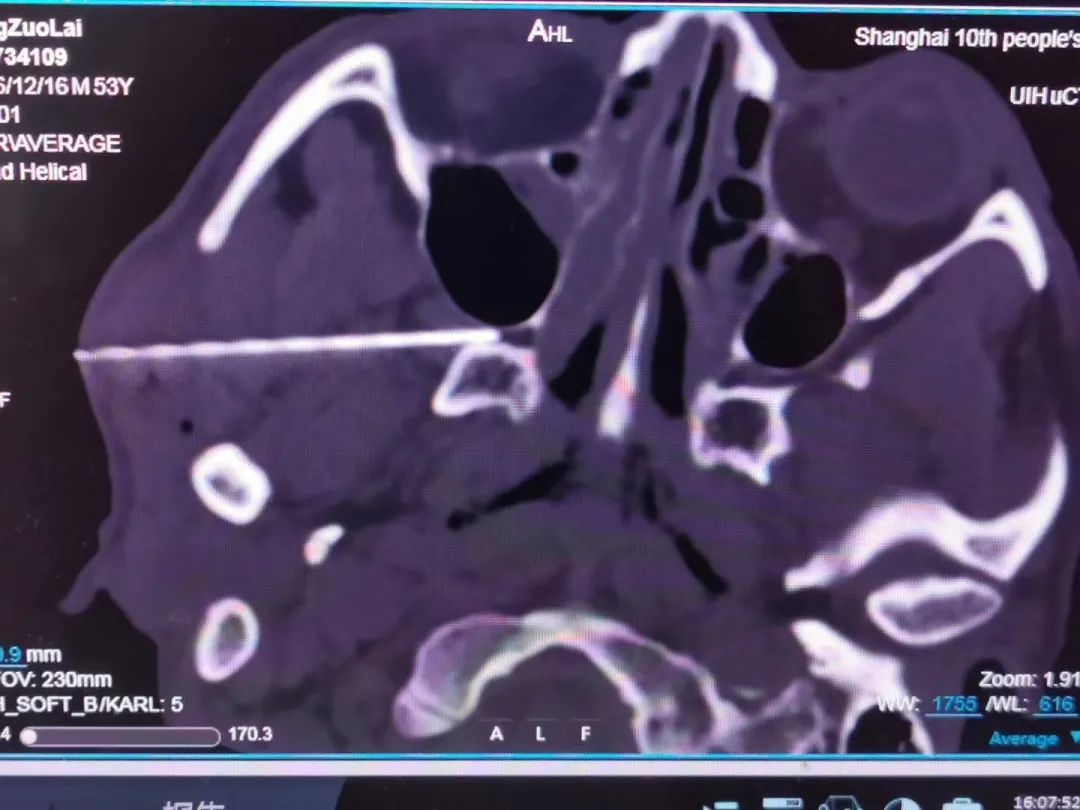

蝶腭神经节附近结构复杂,但在超声联合CT引导下,一般不会发生不良反应和意外。

一根针,一个穴,超声联合CT引导下治疗过程仅需15分钟。